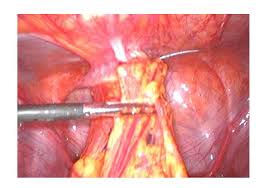

These procedures are usually not done out of medical necessity; An in office hyseroscopic removal was done. Add modifier 51 to 58300 if you do a removal and insertion procedure code z30.430 for insertion only z30.432 for removal only z30.433 for removal and insertion of device to bill for the device mirena device j7298 to bill for the device under nexgen: Subsequently, question is, how do i know if my insurance covers my iud? What is the cpt code for hysteroscopy with removal of iud?

Decoding Coding Office Hysteroscopy Newsscope from newsscope.aagl.org Can i bill 58301 for iud removal and bill 58300 for iud insertion on the same day, if the provider removes and then inserts another iud? Yes, there is no cci edit for those two codes. As for the e/m, it. 97.71 (removal of intrauterine contraceptive device) although some cpt codes are combination codes (e.g., code 11983 for a subcutaneous drug delivery implant removed and reinserted at the same time) the cpt manual does not include a code that represents both an iud insertion and an iud removal performed on the same day. As the iud is pulled out of the uterus, the flexible arms fold. Using ringed forceps, the iud string was grasped and the device was removed without difficulty. The health care professional evaluates the uterus and the position of the strings attached to the iud. To remove the iud, your doctor will grasp the threads of the iud with ring forceps.

The speculum was placed and the iud string visualized. To remove the iud, your doctor will grasp the threads of the iud with ring forceps. Same day iud removal and reinsertion when appropriate and supported by documentation, two cpt procedure codes, an e/m code, and a hcpcs supply code are reported for the one visit. What is the cpt code for hysteroscopy with removal of iud? These procedures are usually not done out of medical necessity; She has had the iud in place for (length of time). Go to super bill go to procedure search (bottom left) put j7298 under the procedure code Can i bill 58301 for iud removal and bill 58300 for iud insertion on the same day, if the provider removes and then inserts another iud? Would it be proper for me to use the 58562 code although the iud was not technically embedded. 97.71 (removal of intrauterine contraceptive device) although some cpt codes are combination codes (e.g., code 11983 for a subcutaneous drug delivery implant removed and reinserted at the same time) the cpt manual does not include a code that represents both an iud insertion and an iud removal performed on the same day. An in office hyseroscopic removal was done. You would use procedure code 58562 (hysteroscopy, surgical; Usually, mirena removal is a routine procedure.